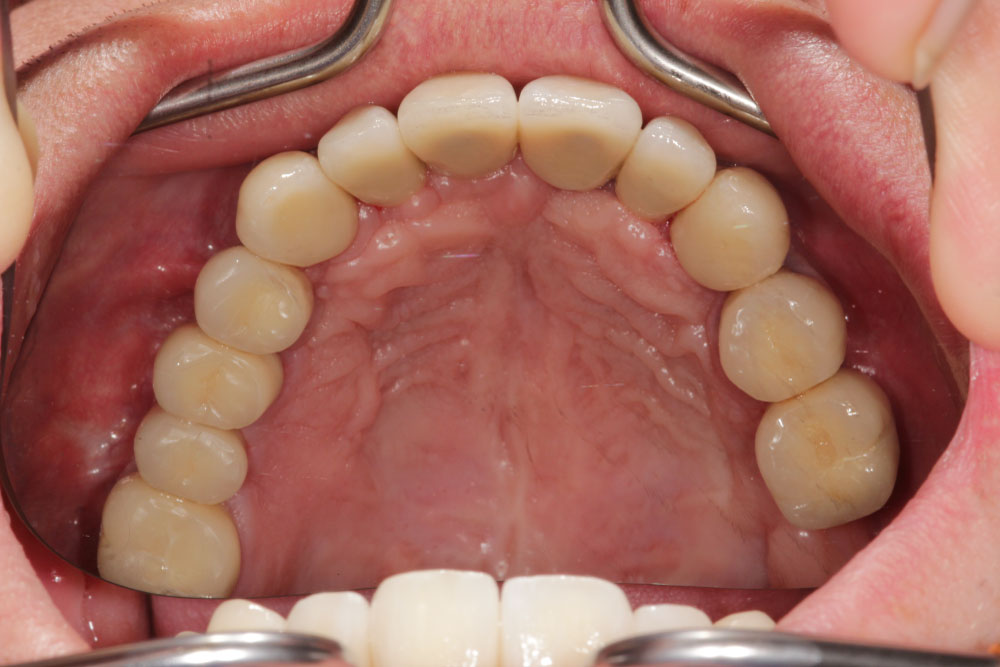

In November 2007, a male patient with ICD10 (K00.0; K07.1) asked for treatment. The diagnosis included craniomandibular malfunction, dysgnathia class III, maxillary retrognathia with horizontal and transverse narrowing of the maxilla, mandibular prognathia with lingual tipping of the mandibular front teeth (Figure 1). Additionally, we diagnosed multiple missing of permanent teeth and hypodontia of deciduous teeth with cones (Figure 2, Figure 3 and Figure 4). Systemically, the patient suffered from platelet deficiency and thrombocytopenia.

Figure 2: Intraoral view pf the patient: Maxillary retrognathia, multiple missing teeth and hypodontia of deciduous teeth before treatment. View Figure 2

Figure 13: Intraoral maxillary situation after cemented single crown restorations on natural teeth and implants. View Figure 13

Figure 14: Intraoral mandibular dental restoration with single crowns on natural teeth and implants. View Figure 14